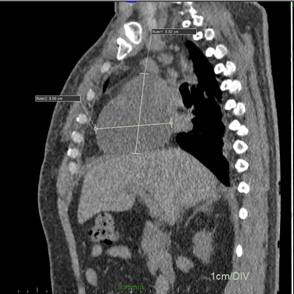

The differentials considered were intracardiac right atrial thrombus, localised pericardial effusion and extracardiac mediastinal bleed in view of recent surgery and use of anticoagulants, antiplatelets. To differentiate above conditions, Computerised Tomography (CT) scan of the chest considered which revealed a mediastinal hematoma of 8.8 x 8.0 cms external to right atrium causing invagination into the RA causing right atrial tamponade (Figures 3,4). He underwent exploratory surgery on the 10th postoperative day, during which the bleed was evacuated, normalizing right atrial function and relieving the inlet obstruction on the RV.

Figure 4: Computerized tomographic sagittal view of right atrial extra cardiac collection of 8.8 x 8.0 cms.